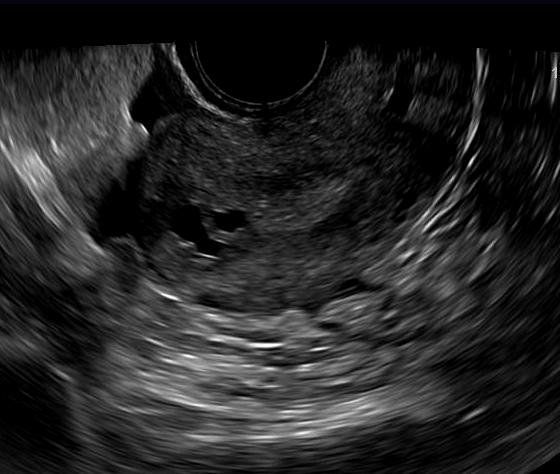

This is a confirmed case of scar ectopic pregnancy. Yesterday, I carried out this exam in an emergency room, without much time to perform an adequate sonogram, the patient did not feel good with “cramps” but no signs of bleeding.